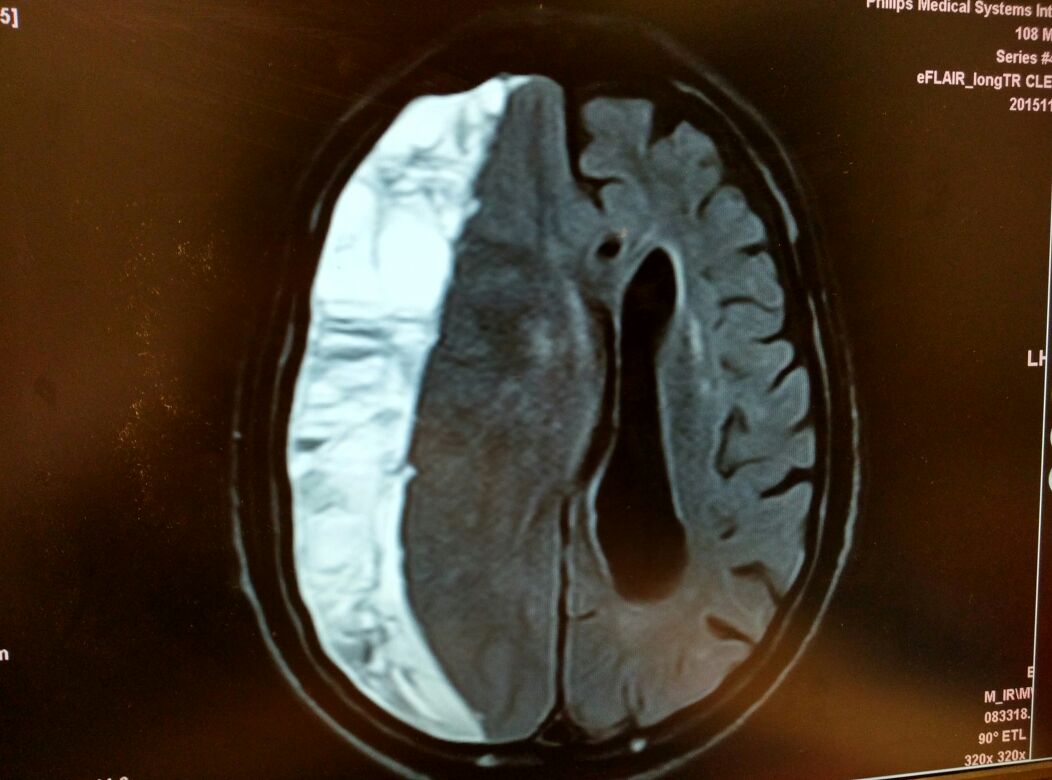

大家看看怎么治疗,需要手术吗

患者男,,65岁,既往体健,因车祸外伤后引起头裂伤入院,头颅ct未见明显异常,胸部ct提示右侧第九肋骨折,目前头部伤口已拆线,胸腹带固定,患者一直诉头晕,眼花,复查头颅ct正常,眼科会诊无异常,大家讨论一下下面怎么弄